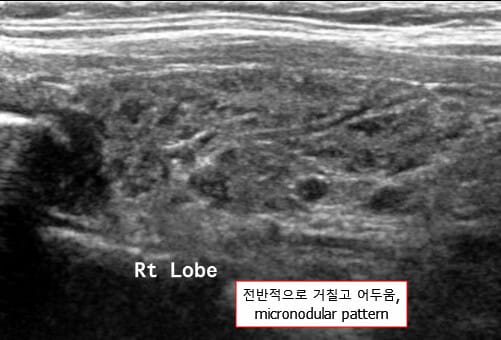

영상 검사 소견

| 영상검사 소견 (초음파) |

| – 갑상선 초음파에서 저에코성 변화 |

| 염증과 섬유화로 인해 정상 조직보다 음파 반사가 적어 저에코성(hypoechoic)으로 보입니다. |

| – 갑상선 크기 불균일 및 결절성 변화 |

| 만성 염증으로 갑상선 조직이 불규칙하게 섬유화되고 결절성 변화를 일으켜 크기가 균일하지 않게 보입니다. |